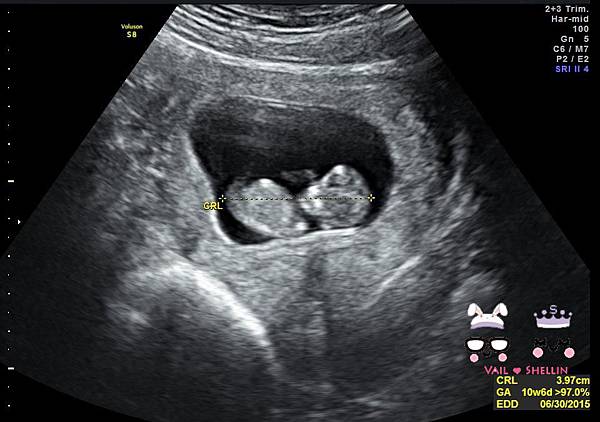

寶寶3.97CM

比兩週前1.97大了兩公分~

比生理期大了6天~XD